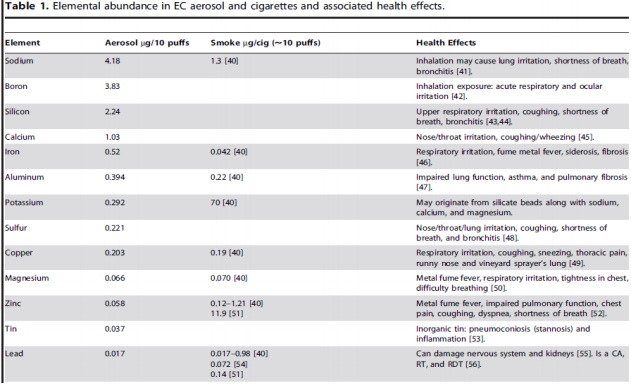

В следующей таблице сравнили содержание тяжелых металлов в электронных сигаретах (показатели во втором столбце) и в обычных (показатели в третьем столбце). Как можно заметить, в паре от электронных сигарет по многим позициям больше тяжелых металлов:

Однако эти значения довольно незначительны. Для сравнения, Доктор Фарсалинос сопоставил их содержание с разрешимым в медицине порогом для медицинских ингаляторов: